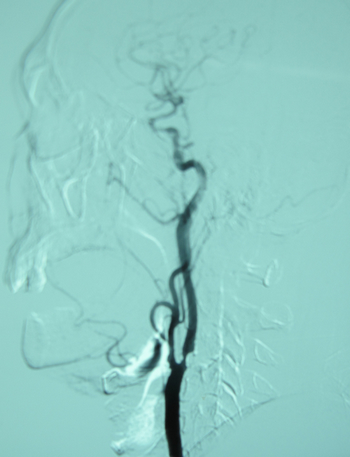

患者司某某,男,57岁,主因“突发右侧肢体无力一月余”入院。患者一月余前无明显诱因出现右侧肢体无力伴交流障碍,于人民医院急诊科就诊,查CT示“左侧颞顶叶、岛叶新发梗塞,收入院后进一步查DSA示:左侧颈总及颈内动脉粥样硬化改变,右侧颈内动脉虹吸段管腔重度狭窄,左侧颈内动脉起始段闭塞,基底动脉闭塞,双侧大脑前动脉A1段闭塞。内科给予改善脑循环、抗血小板聚集、抗动脉粥样硬化等治疗,肢体无力改善,但不能熟练完成发病前经常从事的动作,仍伴交流障碍。为进一步诊治收住院。

患者吴某某,男,63岁,主因“发作性左眼黒曚伴右侧肢体无力半年”入院。患者半年前无明显诱因出现左眼黒曚,伴右侧上下肢活动不利,持续3-5分钟后症状自行缓解,平均每天发作2-3次,就诊于人民医院,完善颈动脉超声、透露MRA等检查提示:颈动脉狭窄,粥样硬化。进一步查DSA:右颈内动脉起始段管腔重度狭窄,左颈内动脉起始段闭塞。给予拜阿司匹林、立普妥口服,上述症状仍间断发作,近一个月来患者症状发作持续时间较前延长,有时长达3小时,收住院拟行颈动脉内膜剥脱术。